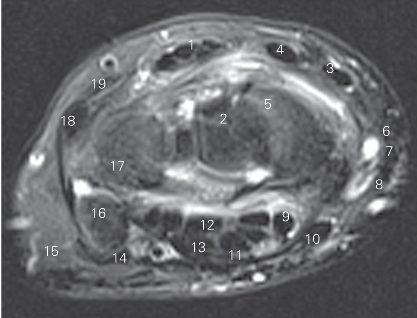

图4-43 经远侧列腕骨远侧份的横断层MR T2WI FS

1 指伸肌腱 tendon of extensor digitorum 2 头状骨capitate bone

3 桡侧腕长伸肌腱 tendon of extensor carpi radialis longus

4 桡侧腕短伸肌腱 tendon of extensor carpi radialis brevis

5 舟骨scaphoid bone

6 拇长伸肌腱 tendon of extensor pollicis longus

7 拇短伸肌腱 tendon of extensor pollicis brevis

8 拇长展肌腱 tendon of abductor pollicis longus

9 拇长屈肌腱 tendon of flexor pollicis longus

10 桡侧腕屈肌腱 tendon of flexor carpi radialis

11 腕管支持带tenaculum of carpal canal

12 指深屈肌腱 tendon of flexor digitorum profundus

13 指浅屈肌腱 tendon of flexor digitorum superficialis

14 尺侧腕屈肌腱 tendon of flexor carpi ulnaris 15 小鱼际hypothenar

16 豌豆骨pisiform bone 17 三角骨triquetral bone

18 尺侧腕伸肌腱 tendon of extensor carpi ulnaris

19 小指伸肌腱 tendon of extensor digiti minimi